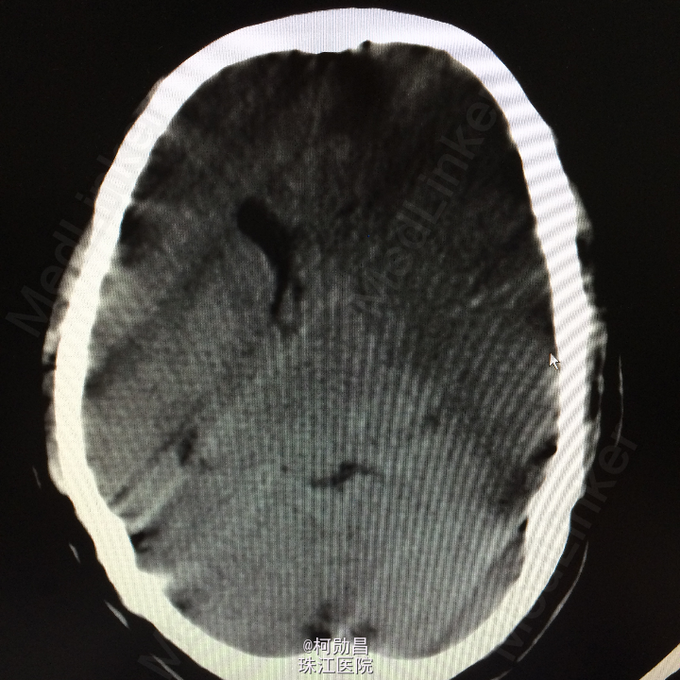

主诉:突发言语不能伴右侧肢体无力1天余 病史:患者于1天前无明显诱因突发言语不能,伴右侧肢体无力,表现为右侧肢体不能自主活动,无头痛头晕,无恶心呕吐,无肢体麻木、四肢抽搐、意识不清等症状。于当地医院就诊,查头颅CT提示:未见异常,予对症支持治疗,症状无好转。半天前患者症状加重,出现神志不清,呈嗜睡状态,现患者为求进一步诊治,遂至我院。门诊拟以“大面积脑梗塞”收入院。

查体:神志呈昏睡状态,言语不能,精神差,双侧瞳孔不等大,左侧3mm,对光反射消失;右侧瞳孔2,mm,对光反射灵敏,右侧肢体肌力0级,左侧肢体肌力5级,右侧肢体肌张力减低,余未见异常。 辅助检查:左侧大脑半球累计岛叶、基底节区(以颞顶叶为主)大片状低密度影,考虑脑梗塞;中线结构明显右移。

诊断:大面积脑梗 处理:予对症支持治疗,运用抗血小板治疗,抗凝治疗